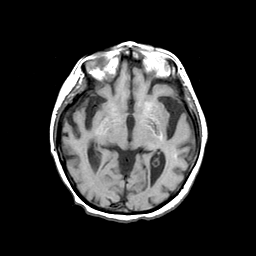

Basal Ganglia Calcification: T1-weighted MR -- Slice #8

[Home][Help][Clinical] Slice 8